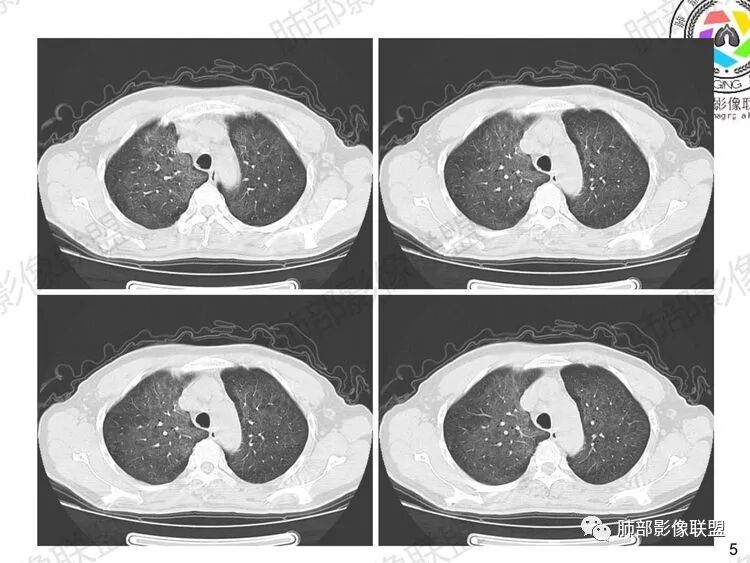

中期:孢子菌在肺泡腔内大量繁殖,引起炎性渗出及肺泡上皮增生,肺泡液内含有滋养体的嗜酸性渗出物及纤维蛋白和脱落的上皮细胞,Ⅱ型肺泡上皮细胞增殖修复受损的肺泡毛细血管间膜,肺间质内巨噬细胞、浆细胞和淋巴细胞增殖导致间质性肺炎,就是说有肺泡腔的密度增高,也有间质的增厚,整个肺受累区域密度都增高,形成以肺门为中心双侧对称的弥漫性磨玻璃样改变,胸膜下较少累及,呈典型的月弓征,采用积极的对症治疗后,大多数病变可吸收消失。

注意肺孢子菌肺炎的肺部影像看上去比较“干”,不会呈现重力趋势。肺血管影及支气管影都比较清楚,尤其是含气支气管影,常常会衬托得格外清晰。

1、双肺从中心向外周对称性弥漫分布的磨玻璃密度影,无重力分布特点

2、中内带分布为主,胸膜下较少受累,可见月弓征

3、下肺纤维灶形成

结合患者症状典型的呼吸困难症状及影像学改变,临床症状轻,影像重,双肺从中心向外周对称性弥漫分布的磨玻璃影,无重力分布,胸膜下受累不明显(月弓征),呈典型的间质性改变,需要考虑肺孢子菌肺炎的可能,临床上需要结合有无HIV、使用免疫抑制剂病史、器官移植等免疫缺陷病史,还可以借助化验CD4细胞、LDH等进一步判断病情。